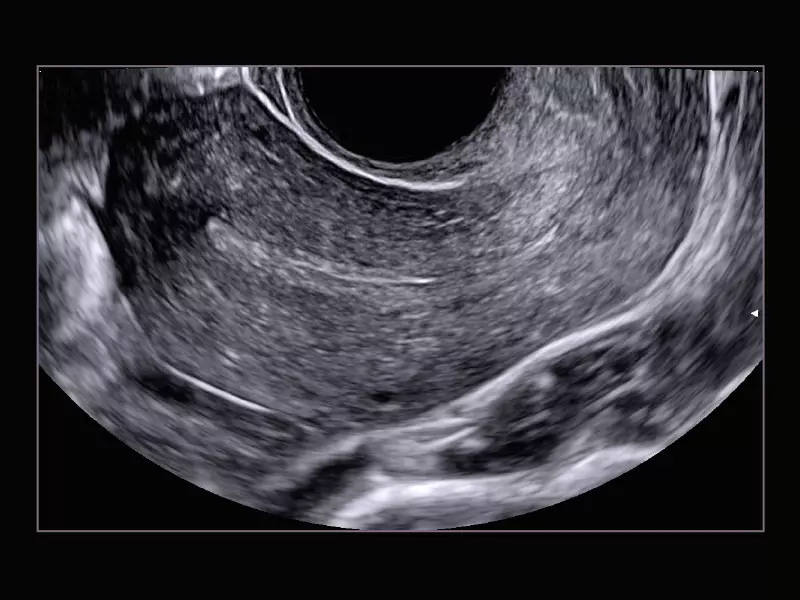

Q7 - Endo

Q7 - Endo

MyLab™X1 Go - WH Endometrium

MyLab™X1 Go - WH Endometrium

MyLab™X1 Go - Gyn

MyLab™X1 Go - Gyn